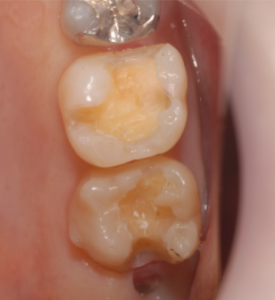

治療前です。

茶色の虫歯が見えます。

齲蝕検知液で染め出します。

赤く染まった部分が虫歯です。

完全に取り除きました。